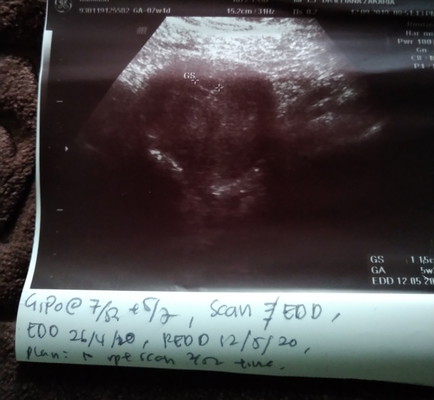

Ikut date sepatutnya sy dah 7weeks 1day masa scan . tp doc scan baru 5weeks 2day . nampak la kantung kecik . Mungkin tarikh last period salah . sbb sblm ni mmg kurang teratur period sy . tapi... doc kata rahim sy mcm bengkak . mcm fibroid tp x sure lg katanya . huhuhu . trus xtau mau ckp apa . Entahla . nnt kita jumpa doc lg ya next 2 weeks . semoga baik² d dalam ya nak... :') #Babyfirst ? #SemogaAllahmudahkan